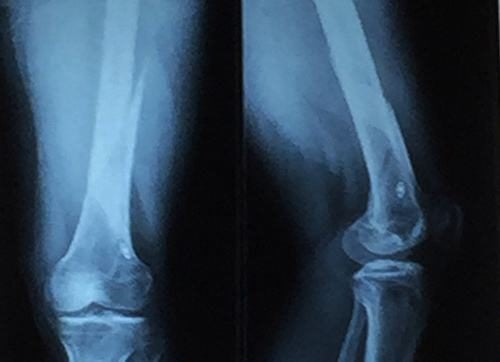

Cách Nhận biết Trật Khớp Khuỷu tay & Phương pháp Điều Trị

Trật khớp khuỷu tay là chấn thương nguy hiểm có thể gây tàn phế suốt đời nếu không nhận biết sớm và xử trí đúng cách. Vậy nhận biết trật khớp khuỷu tay như thế nào và phương pháp nào điều trị mang lại hiệu quả tối ưu nhất hiện nay sẽ được tư vấn […]